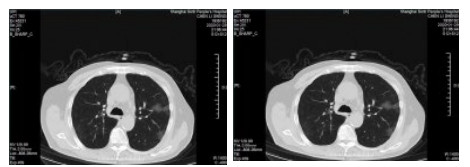

| 图 6 患者,女性,55岁,既往体健,沪籍,无明确武汉流行病学接触史。发热6 d,伴咳嗽,体温39.4℃,伴肌肉酸痛,流感病毒A型IgM阳性,抗柯萨奇病毒IgM阳性,新型冠状病毒核酸检测阴性。肺部CT提示双肺散在磨玻璃结节,部分贴近胸膜。诊断甲型流感病毒性肺炎 Fig 6 Case 6, female, 55 years old, born in Shanghai, was physically healthy, and had no clear history of epidemic exposure of Wuhan. She had fever for 6 days, body temperature was 39.4 ℃, with cough, muscle ache, positive influenza A IgM and anti Coxsackie IgM, negative novel coronavirus nucleic acid test. Lung CT showed ground glass nodules were scattered in bilateral lungs, some of which were close to pleura. She was diagnosed as influenza A virus pneumonia |

| 图 7 患者,女性,36岁,沪籍,有武汉流行病学接触史。发热8 d伴咳嗽,咳痰,有头胀痛,体温38.5℃, 白细胞总数21.8×109/L,淋巴细胞计数10.4%,甲型流感筛查阴性,流感病毒B型IgM阳性,新型冠状病毒核酸检测2次阴性。肺部CT提示双肺多发团片影,实变及磨玻璃结节,伴支气管充气征。诊断乙型流感病毒性肺炎 Fig 7 Case 7, female, 36 years old, born in Shanghai, with a history of epidemic exposure of Wuhan. She had fever for 8 days with cough, expectoration, head pain, body temperature of 38.5℃, total white blood cells of 21.8×109/L, lymphocyte count of 10.4%, negative influenza A virus screening, positive influenza B IgM, and negative novel coronavirus nucleic acid test for twice. Lung CT showed multiple mass shadows, consolidation and ground glass nodule in both lungs, accompanied by bronchiectasis. She was diagnosed as influenza B pneumonia |

| 图 8 患者,男性,20岁,湖北籍,发病前6 d有武汉流行病学接触史,发热,体温39.3℃,有干咳,血白细胞总数及淋巴计数正常,甲型、乙型流感病毒抗原筛查阴性以及其他呼吸道常规病毒筛查阴性,新型冠状病毒核酸检测2次阴性。肺部CT提示左下肺磨玻璃结节,贴近胸膜,可见铺路石征,小叶间胸膜增厚。病因不明 Fig 8 Case 8, male, 20 years old, born in Hubei Province, had a history of epidemic exposure of Wuhan 6 days before the onset of the disease. He had fever with a body temperature of 39.3 ℃, dry cough, normal WBC and lymph count, negative influenza A and B virus screening, and other routine respiratory virus screening, negative novel coronavirus nucleic acid test for twice. Lung CT showed ground glass nodule of the lower left lung, close to the pleura, with paving stone sign and thickening of interlobular pleura. Unknown etiology |